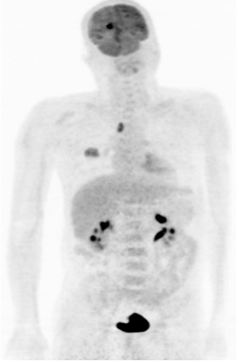

3. Chụp PET/CT

Là phương pháp rất có giá trị trong việc phát hiện các tổn thương di căn nói chung, trong đó có di căn não. Pỹ thuật này có nhiều ưu điểm:

• Tìm u nguyên phát của di căn não

• Đánh giá giai đoạn bệnh chính xác

• Đánh giá hiệu quả của việc điều trị

• Theo dõi, phát hiện tái phát, di căn

• Hướng dẫn cho việc sinh thiết tổn thương

• Lập kế hoạch xạ trị

Trong chẩn đoán di căn não, dược chất phóng xạ thường được sử dụng là TC-99m. Trường hợp điển hình: hình ảnh tổn thương tăng hoạt tính phóng xạ.

Theo Virani (2009); Virani (2009) thì độ nhạy của FDG-PET/CT trong việc phát hiện di căn não là 97,8% so với chụp cộng hưởng từ sọ não, có 35,9% bệnh nhân không có triệu chứng thần kinh được phát hiện di căn não bằng FDG-PET/CT.

Hình 7. Hình ảnh di căn não của bệnh nhân ung thư phổi không phải tế bào nhỏ được phát hiện trên PET/CT tại Trung tâm Y học hạt nhân và ung bướu, Bệnh viện Bạch Mai.